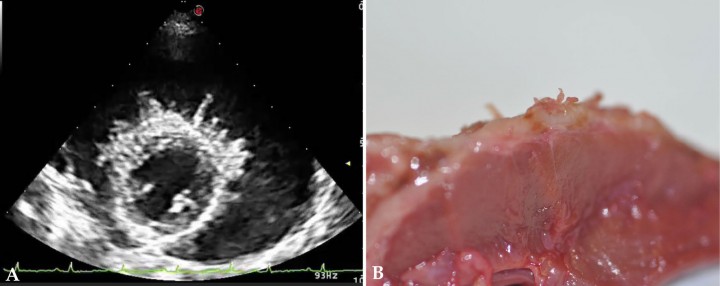

Tanto el tamaño como la localización puede ayudar al diagnóstico, siendo siempre necesario la citología o la toma de biopsias para la confirmación del diagnóstico.[ Rajagopalan V, Jesty SA, Craig LE, Gompf R: Comparison of presuntive echocardiografic and definitive diagnosis of cardiac tumours in dogs. J Vet Intern Med 2013;27(5):1092-6. [PubMed] ] Las masas cardiacas pueden tener cualquier localización cardiaca (Fig. 7).

<p>(<strong>A</strong>) Ecocardiografía en corte paraesternal derecho, eje largo, cuatro cámaras. Imagen compatible con masa en atrio derecho (entre flechas). (<strong>B</strong>) Imagen macroscópica donde se aprecia la visualización de masa en aurícula izquierda <em>post mortem</em>.</p>

(A) Ecocardiografía en corte paraesternal derecho, eje largo, cuatro cámaras. Imagen compatible con masa en atrio derecho (entre flechas). (B) Imagen macroscópica donde se aprecia la visualización de masa en aurícula izquierda post mortem.

1. Masas heterogéneas redondeadas en aurícula derecha (p. ej., hemangiosarcoma) (Fig. 8A).

2. Tumores de base cardiaca (p. ej., quemodectoma), que son de aspecto más homogéneo y se suelen encontrar en el cayado de la aorta o localizados entre el tronco pulmonar y la aorta, observándose sobrecarga de volumen ventricular derecha por colapso de las venas pulmonares (Fig. 8B).

3. Derrame pericárdico con/sin signos de taponamiento cardiaco. En el taponamiento cardiaco observamos colapso de la pared libre del atrio y/o del ventrículo derecho. Un taponamiento grave puede producir una reducción del volumen del ventrículo izquierdo apreciándose una pseudohipertrofia de ventrículo izquierdo (Fig. 8C).

4. Los mesoteliomas o tumores de pequeño tamaño pueden ser más difíciles de visualizar. Sin embargo, ocasionalmente se puede observar, además de derrame pericárdico, pequeños filamentos que surgen del ventrículo izquierdo (Fig. 9).

<p>(<strong>A</strong>) Ecocardiografía en corte paraesternal derecho eje corto, base cardiaca-aorta compatible con masa en atrio derecho. (<strong>B</strong>) Ecocardiografía en corte paraesternal derecho eje corto, base cardiaca-aorta compatible con tumor de base cardiaca. (<strong>C</strong>) Ecocardiografía en corte paraesternal derecho eje corto, ventrículo izquierdo compatible con derrame pericárdico.</p>

(A) Ecocardiografía en corte paraesternal derecho eje corto, base cardiaca-aorta compatible con masa en atrio derecho. (B) Ecocardiografía en corte paraesternal derecho eje corto, base cardiaca-aorta compatible con tumor de base cardiaca. (C) Ecocardiografía en corte paraesternal derecho eje corto, ventrículo izquierdo compatible con derrame pericárdico.

<p>(<strong>A</strong>) Ecocardiografía en eje paraesternal derecho, eje corto, ventrículo izquierdo, compatible con derrame pericárdico y mesotelioma. (<strong>B</strong>) Detalle <em>post mortem</em> de mesotelioma.</p>

(A) Ecocardiografía en eje paraesternal derecho, eje corto, ventrículo izquierdo, compatible con derrame pericárdico y mesotelioma. (B) Detalle post mortem de mesotelioma.